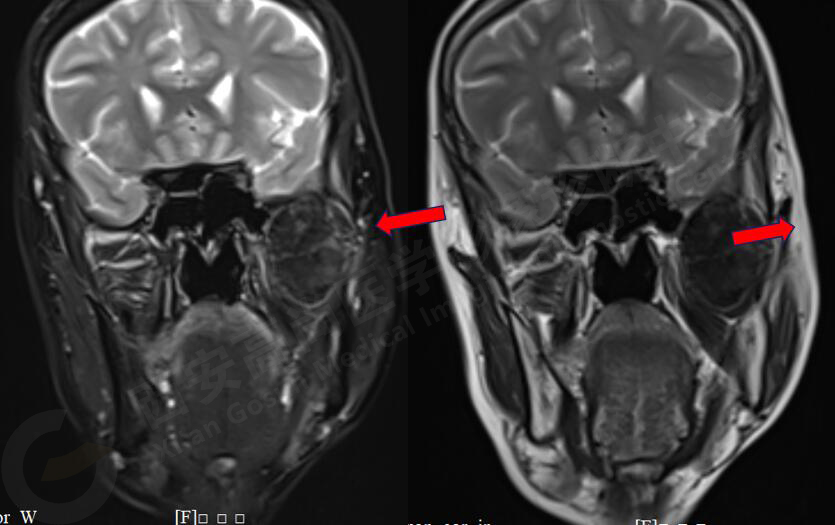

女,58歲,左側(cè)咀嚼肌間隙腫塊,鄰近翼板外側(cè)骨質(zhì)破壞;左側(cè)下頜升支內(nèi)側(cè)占位,皮質(zhì)旁骨軟骨來源。

MR圖像

MR診斷

左側(cè)翼腭窩、顳下窩占位,左側(cè)腮腺受壓變形,頸內(nèi)動脈稍受壓,考慮軟骨組織來源、良性病變。

此腫瘤位于左側(cè)翼腭窩、顳下窩,各序列均呈低信號,與翼突內(nèi)外側(cè)板、下頜骨關(guān)系密切,鄰近下頜骨骨皮質(zhì)破壞,DWI像上呈較高信號,呈不均勻中度強化,因此考慮軟骨來源或肌纖維來源,良性可能性大。